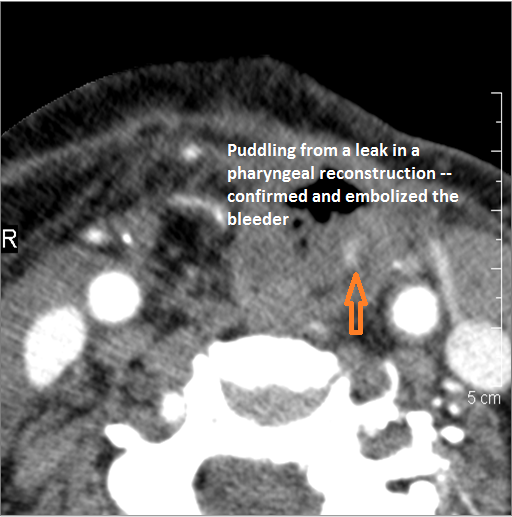

There is evidence of active extravasation from an arterial source